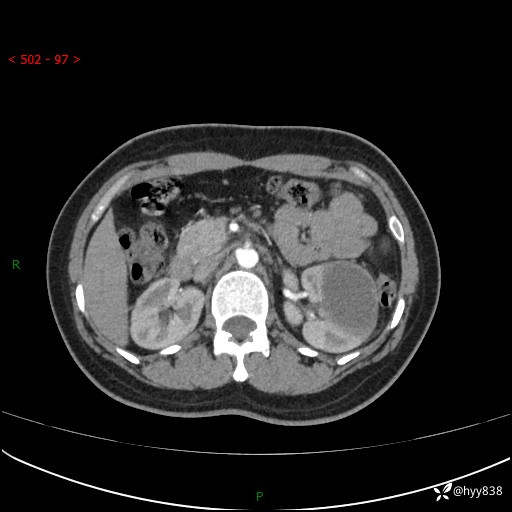

现病史:患者于1周前因左侧腰腹部间断胀痛不适,无恶心呕吐,无明显肉眼血尿,无畏寒发热,无尿频尿急,起病初,患者来我院就诊,查CT提示左肾低密度影,外周血提示:白细胞11.25*10^9/L.行抗感染治疗后未见明显好转,06-18泌尿系增强CT提示左肾类圆形低密度占位(脓肿?肿瘤?),大小:4.0*3.2cm,为求进一步治疗,门诊以“左肾占位”收住我科。 起病以来,患者精神佳,饮食、睡眠良好,大小便正常,体力体重无明显变化。

双肾CT平扫+增强